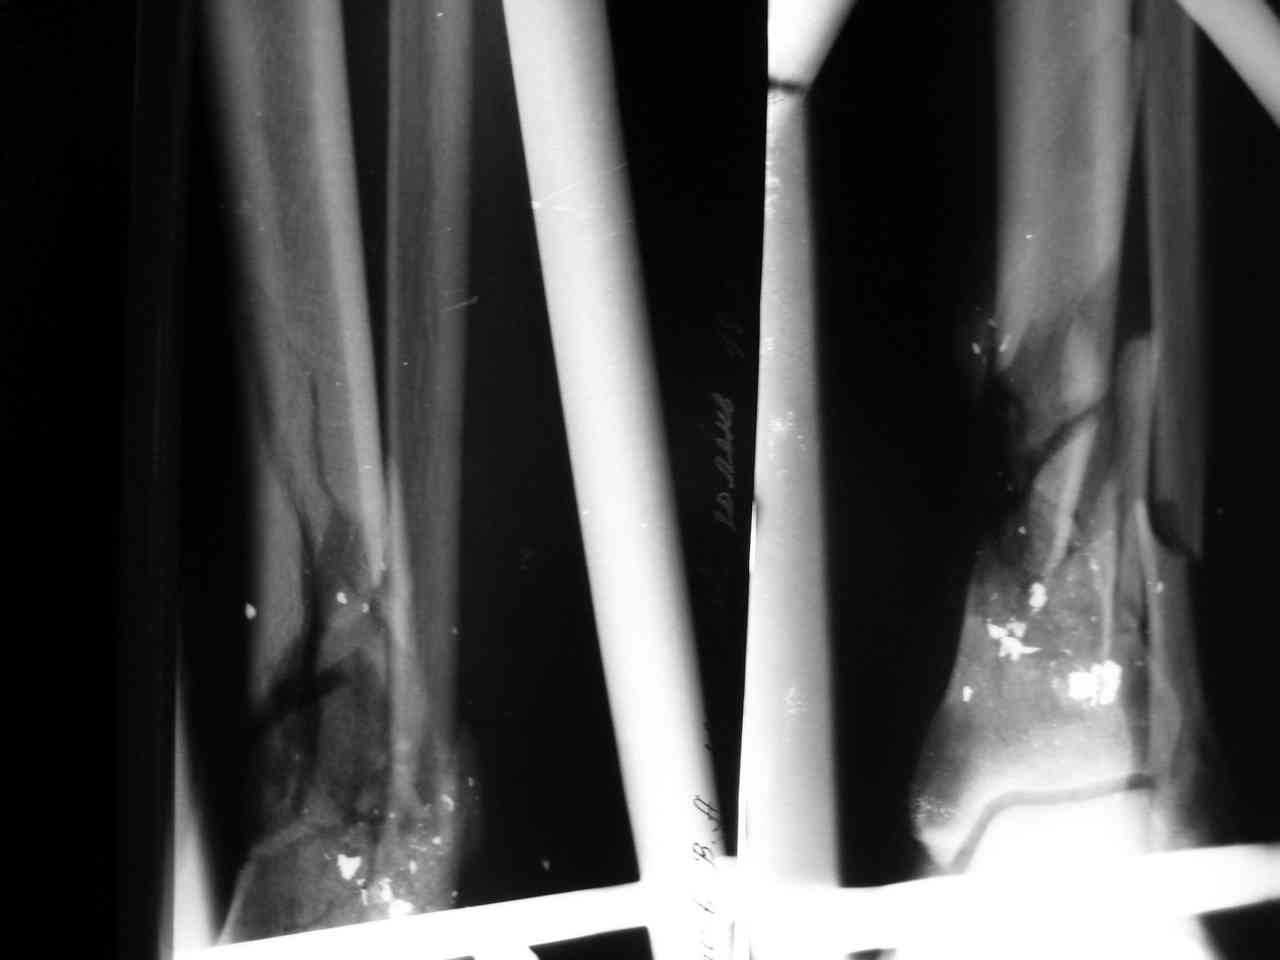

Еще находится в отделении пациент со схожим огнестрельным переломом обеих костей нижней трети голени (классификация Каплана, Марковой относится к неогнестрельным переломам). При поступлении

(26/12/2007)выполнена ПХО перелома: выброшены свободно лежащие осколки, иссечены явно нежизнеспособные ткани, наложен двуплоскостной двустержневой аппарат наружной фиксации. Раны не ушивались. Было повреждение передней большеберцовой артерии, вен. Но стопа оставалась

"живой":теплая на ощупь, сохранялась ее чувствительность, активная подвижноть пальцев. На следующие сукти выполнен second look: удалены абсолютно все осколки (если при поступлении они были интимно фиксированы к мягким тканям, что создало обманчивое впечатление их жизнеспособности, то сутки спустя они все оказались свободнолежащими), выполнено резецирование краев отломков для формирования торцевого упора, налажено сквозное дренирование раны.

В результате мероприятий, в дальнейшем, рана активно гранулировала. Признаков инфекции так и не

возникло. В ходе перевязок было иссечено некротизированное сухожилие глубокого сгибателя Большого пальца. Вчера (25/01/2008) больному

наложен аппарат ЧКДО по Илизарову под билокальный остеосинтез. Как будут снимки - выложу все.